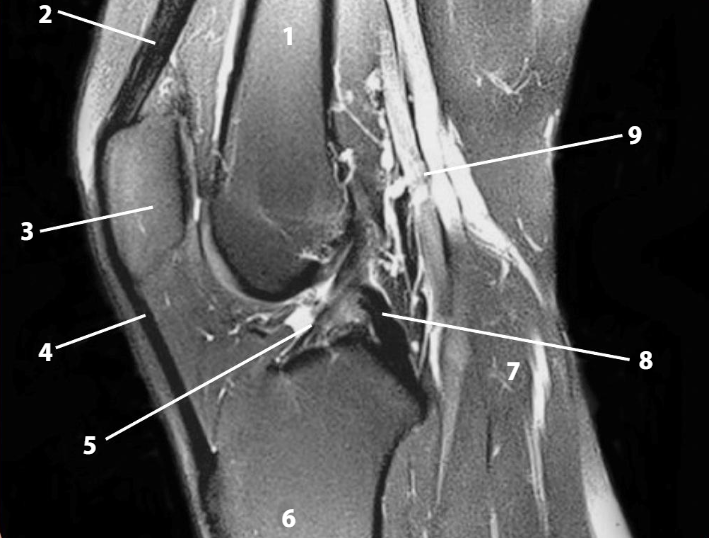

Paciente hombre de 24 años de edad que acude a consulta de traumatología por presentar dolor en la articulación de la rodilla, derrame articular e imposibilidad para realizar movimientos amplios de flexión. El paciente refiere que durante un partido de futbol recibió una barrida que golpeó la rodilla de apoyo por la cara externa y que fue entonces cuando apareció el dolor. Se realiza una exploración física de la siguiente manera: para valorar los meniscos se pide al paciente que se coloque en decúbito supino, se flexiona la rodilla y se coloca el dedo en el borde del menisco, seguido de una extensión en rotación interna y luego se repite en rotación externa; como consecuencia, se despierta dolor y se siente un chasquido en el menisco interno al extender la rodilla en rotación lateral. Para valorar los ligamentos colaterales se extiende la rodilla y se aplica un movimiento de empuje hacia la cara medial con la finalidad de valorar la integridad del menisco lateral, y se empuja desde afuera para valorar el menisco interno; ante ello, se observa una leve abertura en la cara interna de la rodilla, el signo del bostezo. Para valorar los ligamentos cruzados se realizan las pruebas de rutina, las cuales fueron negativas. Se toma una radiografía anteroposterior de la rodilla y una resonancia magnética (RM), donde se confirma una lesión en el menisco interno. Se decide puncionar la articulación para drenar el derrame articular.